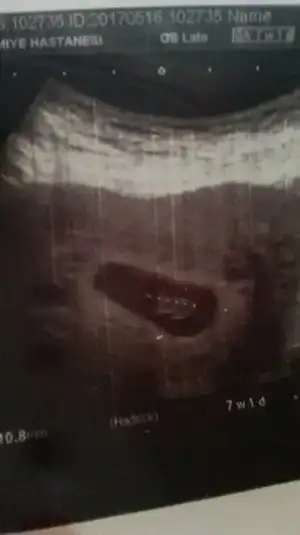

Mrblar bunuda yorumlar mısınız vajinal ultrason

Eklentiler

• IMG_2781.webp

IMG_2781.webp

3,9 KB · Görüntüleme: 105